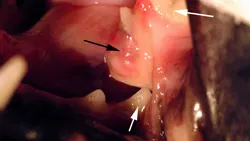

Examination. On presentation, the cat could not close its lower jaw. The mandible had lateralized to the animal's left side. A prominent, open symphyseal fracture covered with granulation tissue (Figure A) was visible, and the cat resisted physical manipulation. The

animal was anesthetized for further evaluation of the oral cavity. An open caudal fracture of the left mandibular ramus was visible between the 4th premolar and the 1st molar (Figure B; white arrows). The mandibular artery had been lacerated, and an organized fibrin clot was present (black arrow). An intraoral occlusal view radiograph was taken of the symphysis, and an extraoral lateral radiograph was taken of the TMJ and horizontal ramus of both right and left sides. A 1-cm separation of the symphysis was visible on the films, but no rostral mandibular fractures were present (Figure C). The left lateral film showed a caudal ramus fracture between the 4th premolar and the 1st molar (Figure D). There was no evidence of roots in the fracture site. This film also showed a left craniodorsal TMJ luxation (black arrows) and a left caudal ramus fracture between the 4th premolar and the 1st molar (white arrows).